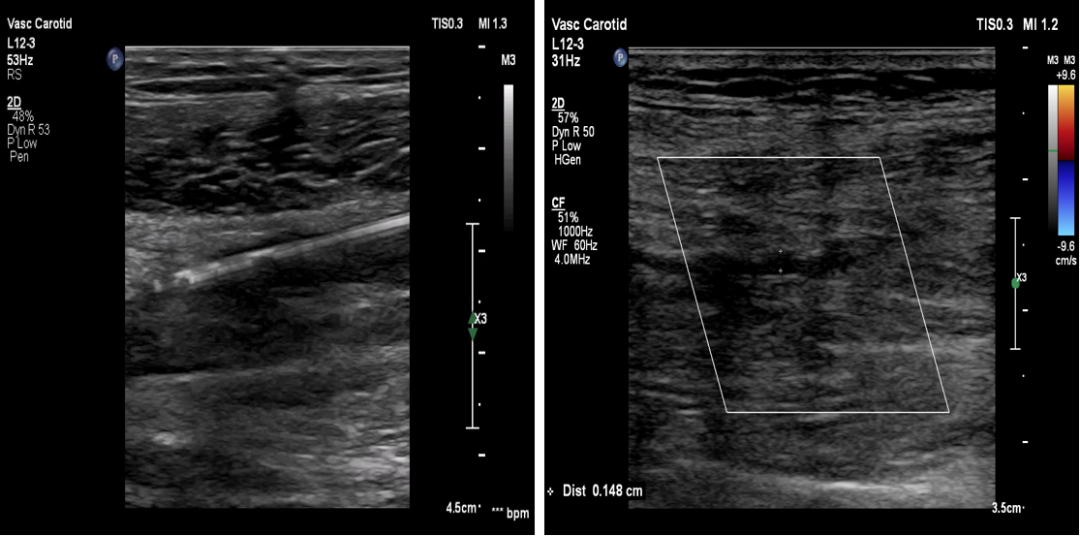

★ 超声引导开通下肢动脉闭塞病变

图:超声图像